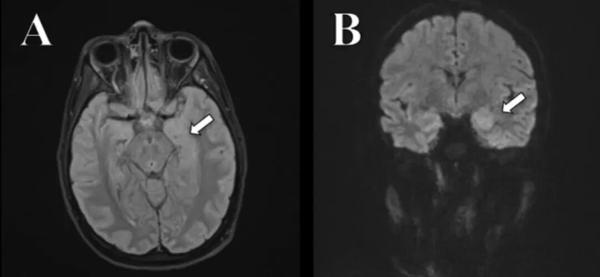

另一个病例是一位24岁女性,她因为急性意识模糊而急诊入院。随着意识迅速恶化,她开始出现吞咽困难、呼吸衰竭和严重的心动过缓。入院第23天,她经由脑部磁共振成像检测,确诊了抗NMDAR脑炎。

患者的海马不对称,出现了炎症 图片来源于论文